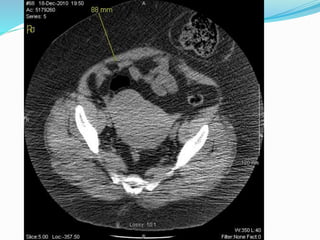

Parastomal hernia

 Incidence is unknown

due to underreporting

and difficult dx.

 Estimated to be between

20-80%

 More frequent with

colostomy than

ileostomy

 Cingi et al

 23 patients

 Patient examination

(PE) detected PSH in

52%

 CT detected total of

78%